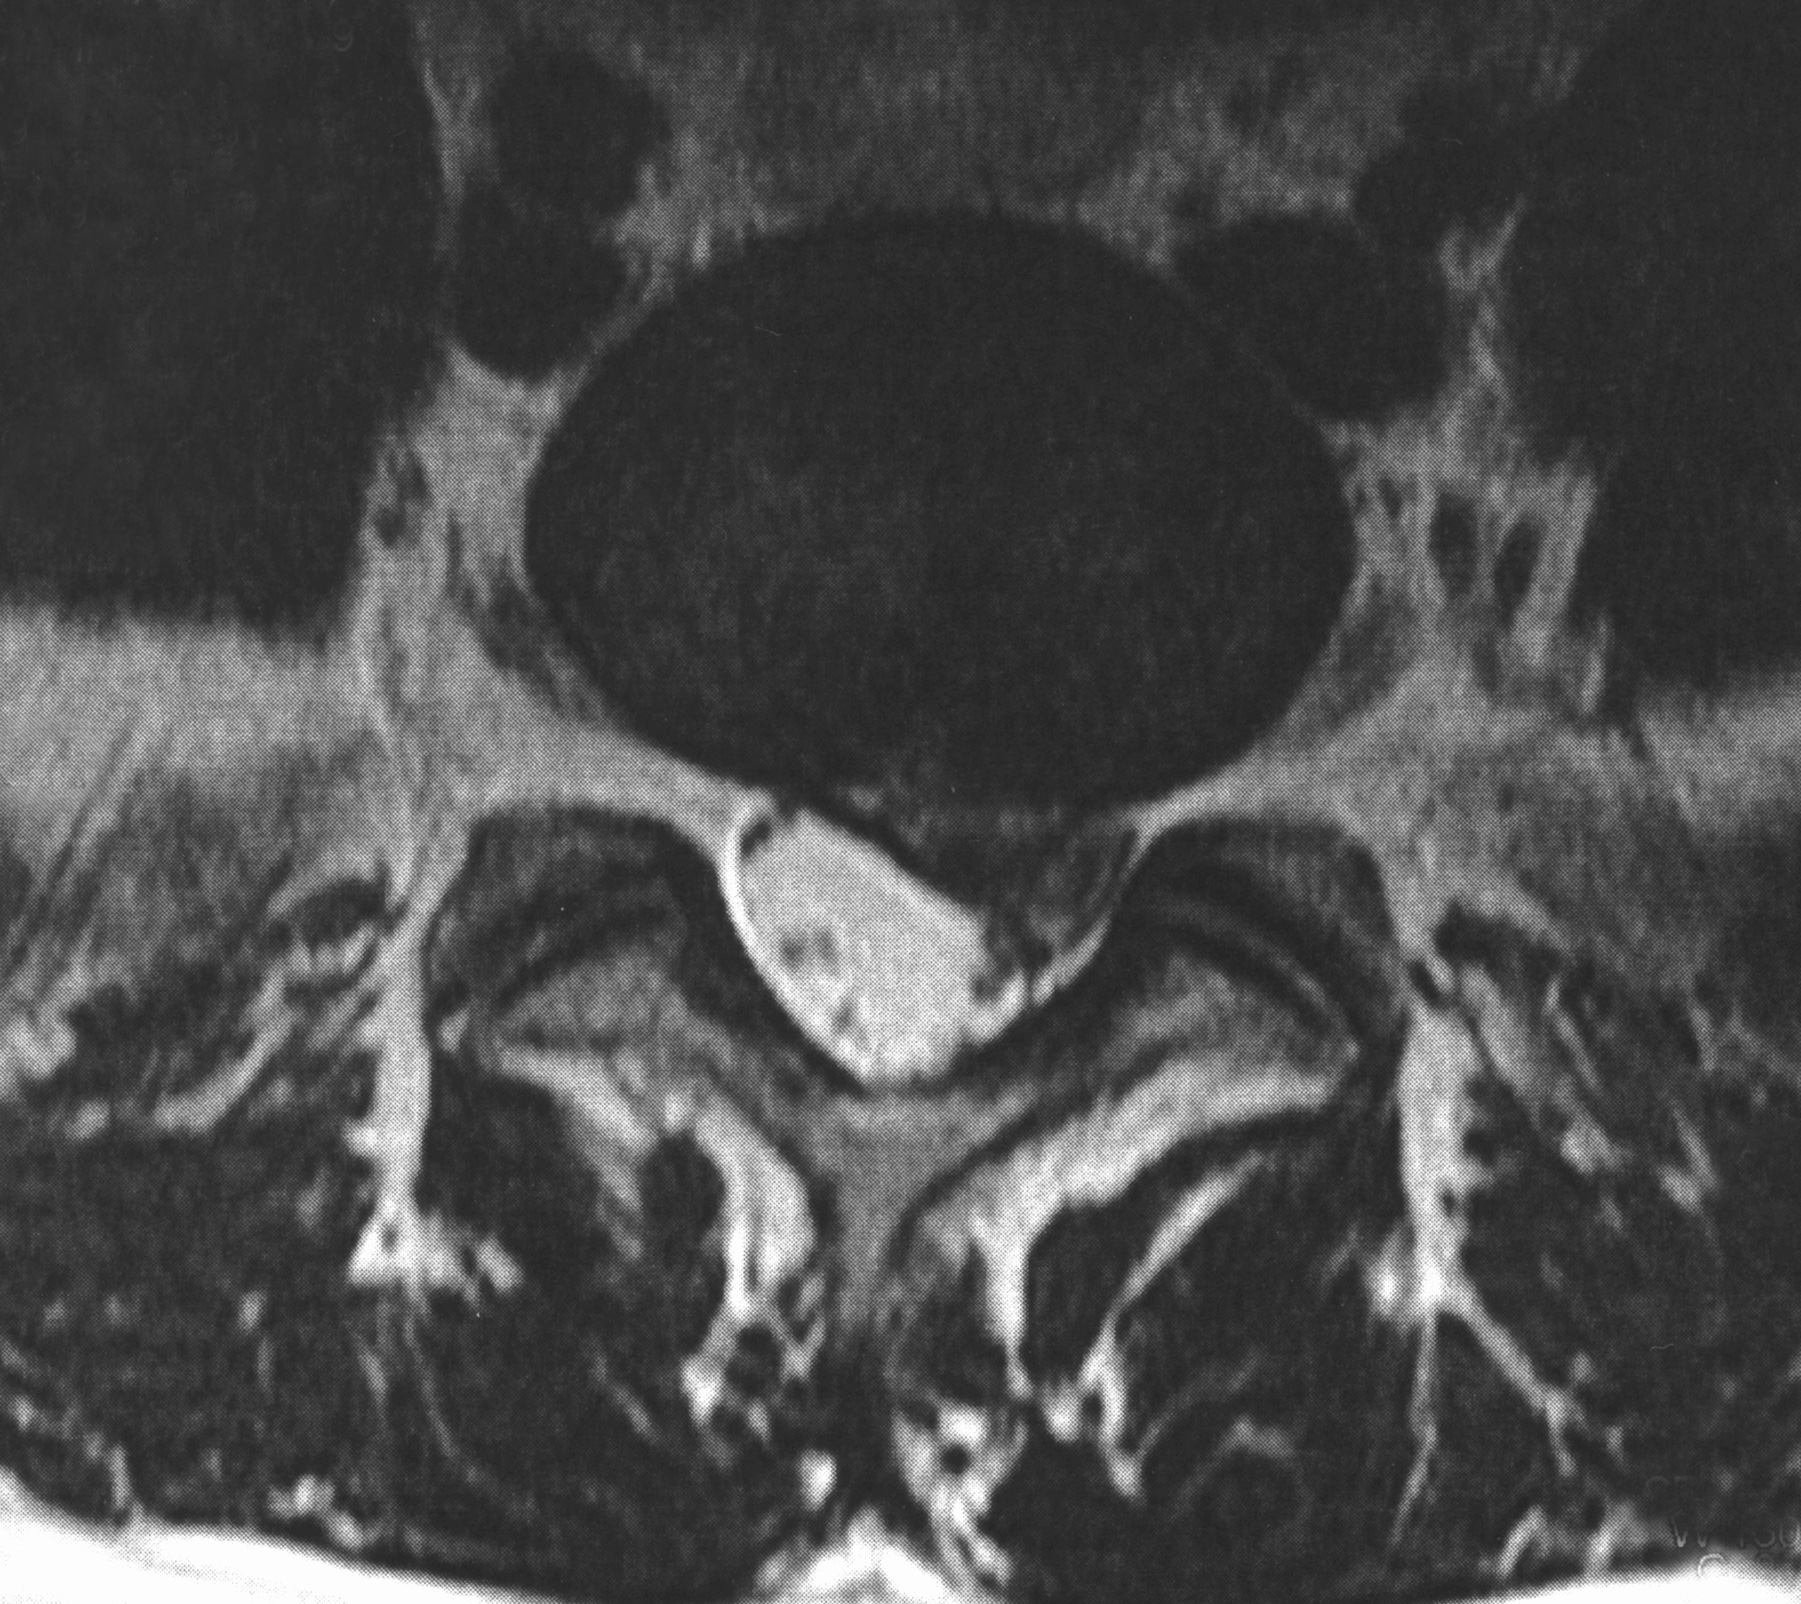

Ich habe mich in meiner Praxis bewusst auf die mikrochirurgische Operation spezialisiert. Dabei wird über einen kleinen Hautschnitt der Zugang zur betroffenen Stelle der Wirbelsäule geschaffen. Unter dem Operationsmikroskop kann ich das in den Wirbelkanal vorgetretene Bandscheibengewebe darstellen und entfernen. So wird die eingeengte Nervenwurzel entlastet, während umliegende Strukturen möglichst geschont bleiben. Der Schnitt ist klein und verheilt in der Regel so, dass die Narbe später unauffällig bleibt.

Was passiert bei einem Bandscheibenvorfall?